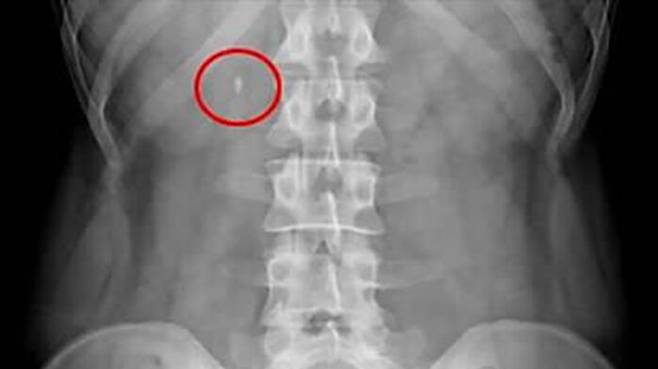

▲ 요로결석 엑스레이

요로결석은 우리 몸속에 소변이 흐르는 길인 신장과 요관, 방광에 돌과 같은 덩어리(결석)가 생겨 소변 길을 막거나 염증을 일으키는 상태를 말합니다.